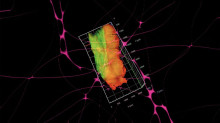

“Detecting cuts is making them” Imaging technologies have been attempting to turn bodies into datasets, to reproduce and simulate a readable and writable volume of bodies in silico. This video speaks of the body, data, and the transformation between them from the embodied perspective of the interstitial fluid, the fluid between cells. Wandering and thinking with the amorphous liquid network of relations circulating around the body, we will look into tissue staining and digital segmentation and their similarities — both reduce ambiguity, build contrast, define structure and make visible. Here visibility becomes a matter of dimension, projection, axis, and rotation. Once turned into data, both corporeal flesh and digital flesh become operable, entering a recursive simulation in which depths and densities can be sliced, false-colored, navigated, enlarged, rotated and stacked back into three dimensions. The materiality of the body is reworked according to the logic of computer storage and computer vision to reproduce a stable, operable body of volume. Bodies into datasets, datasets into flesh, memories into algorithms, algorithms into membranes from collective remembrances.

*Touching Thoughts is an art-science cooperation project the net culture initiative servus.at – Kunst und Kultur im Netz and the JKU’s Medical Faculty (Department of Pathology and Molecular Pathology and Institute of Anatomy and Cell Biology of JKU), that aims at exploring protocols and modes of three-dimensional imaging in the field of digital pathology, and how scientific and medical knowledge and truth are generated through digital technologies.